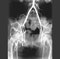

Arteriogram of lower limb vessels 8. Define the popliteal fossa, clean and identify its contents. (Play movie; View images: N 493, 495, 502, 512, 517, 546, TG 3-29, 3-31A, 3-31B, 3-62, 3-70)

Identify the muscles bounding the fossa. Clear the fat and identify the tibial nerve and its medial sural cutaneous branch; also identify the common fibular (peroneal) nerve and its lateral sural cutaneous branch. Note the relationship to the biceps femoris tendon as the nerve courses around the neck of the fibula. Now clear the popliteal vein and trace the lesser saphenous vein to its termination. Explore the popliteal artery, the adductor hiatus and the manner in which the vein and artery enter and leave the popliteal fossa. Where exactly is the popliteal fossa located in the lower extremity?

Surface features of the popliteal fossa Popliteal artery and vein Remove the popliteal vein and expose the popliteal artery. Identify the muscular branches to hamstrings and sural branches. Then locate the superior medial and superior lateral genicular arteries crossing the heads of origin of the gastrocnemius muscles, but lying directly on the bone. Locate a middle genicular artery entering the posterior side of the knee joint.